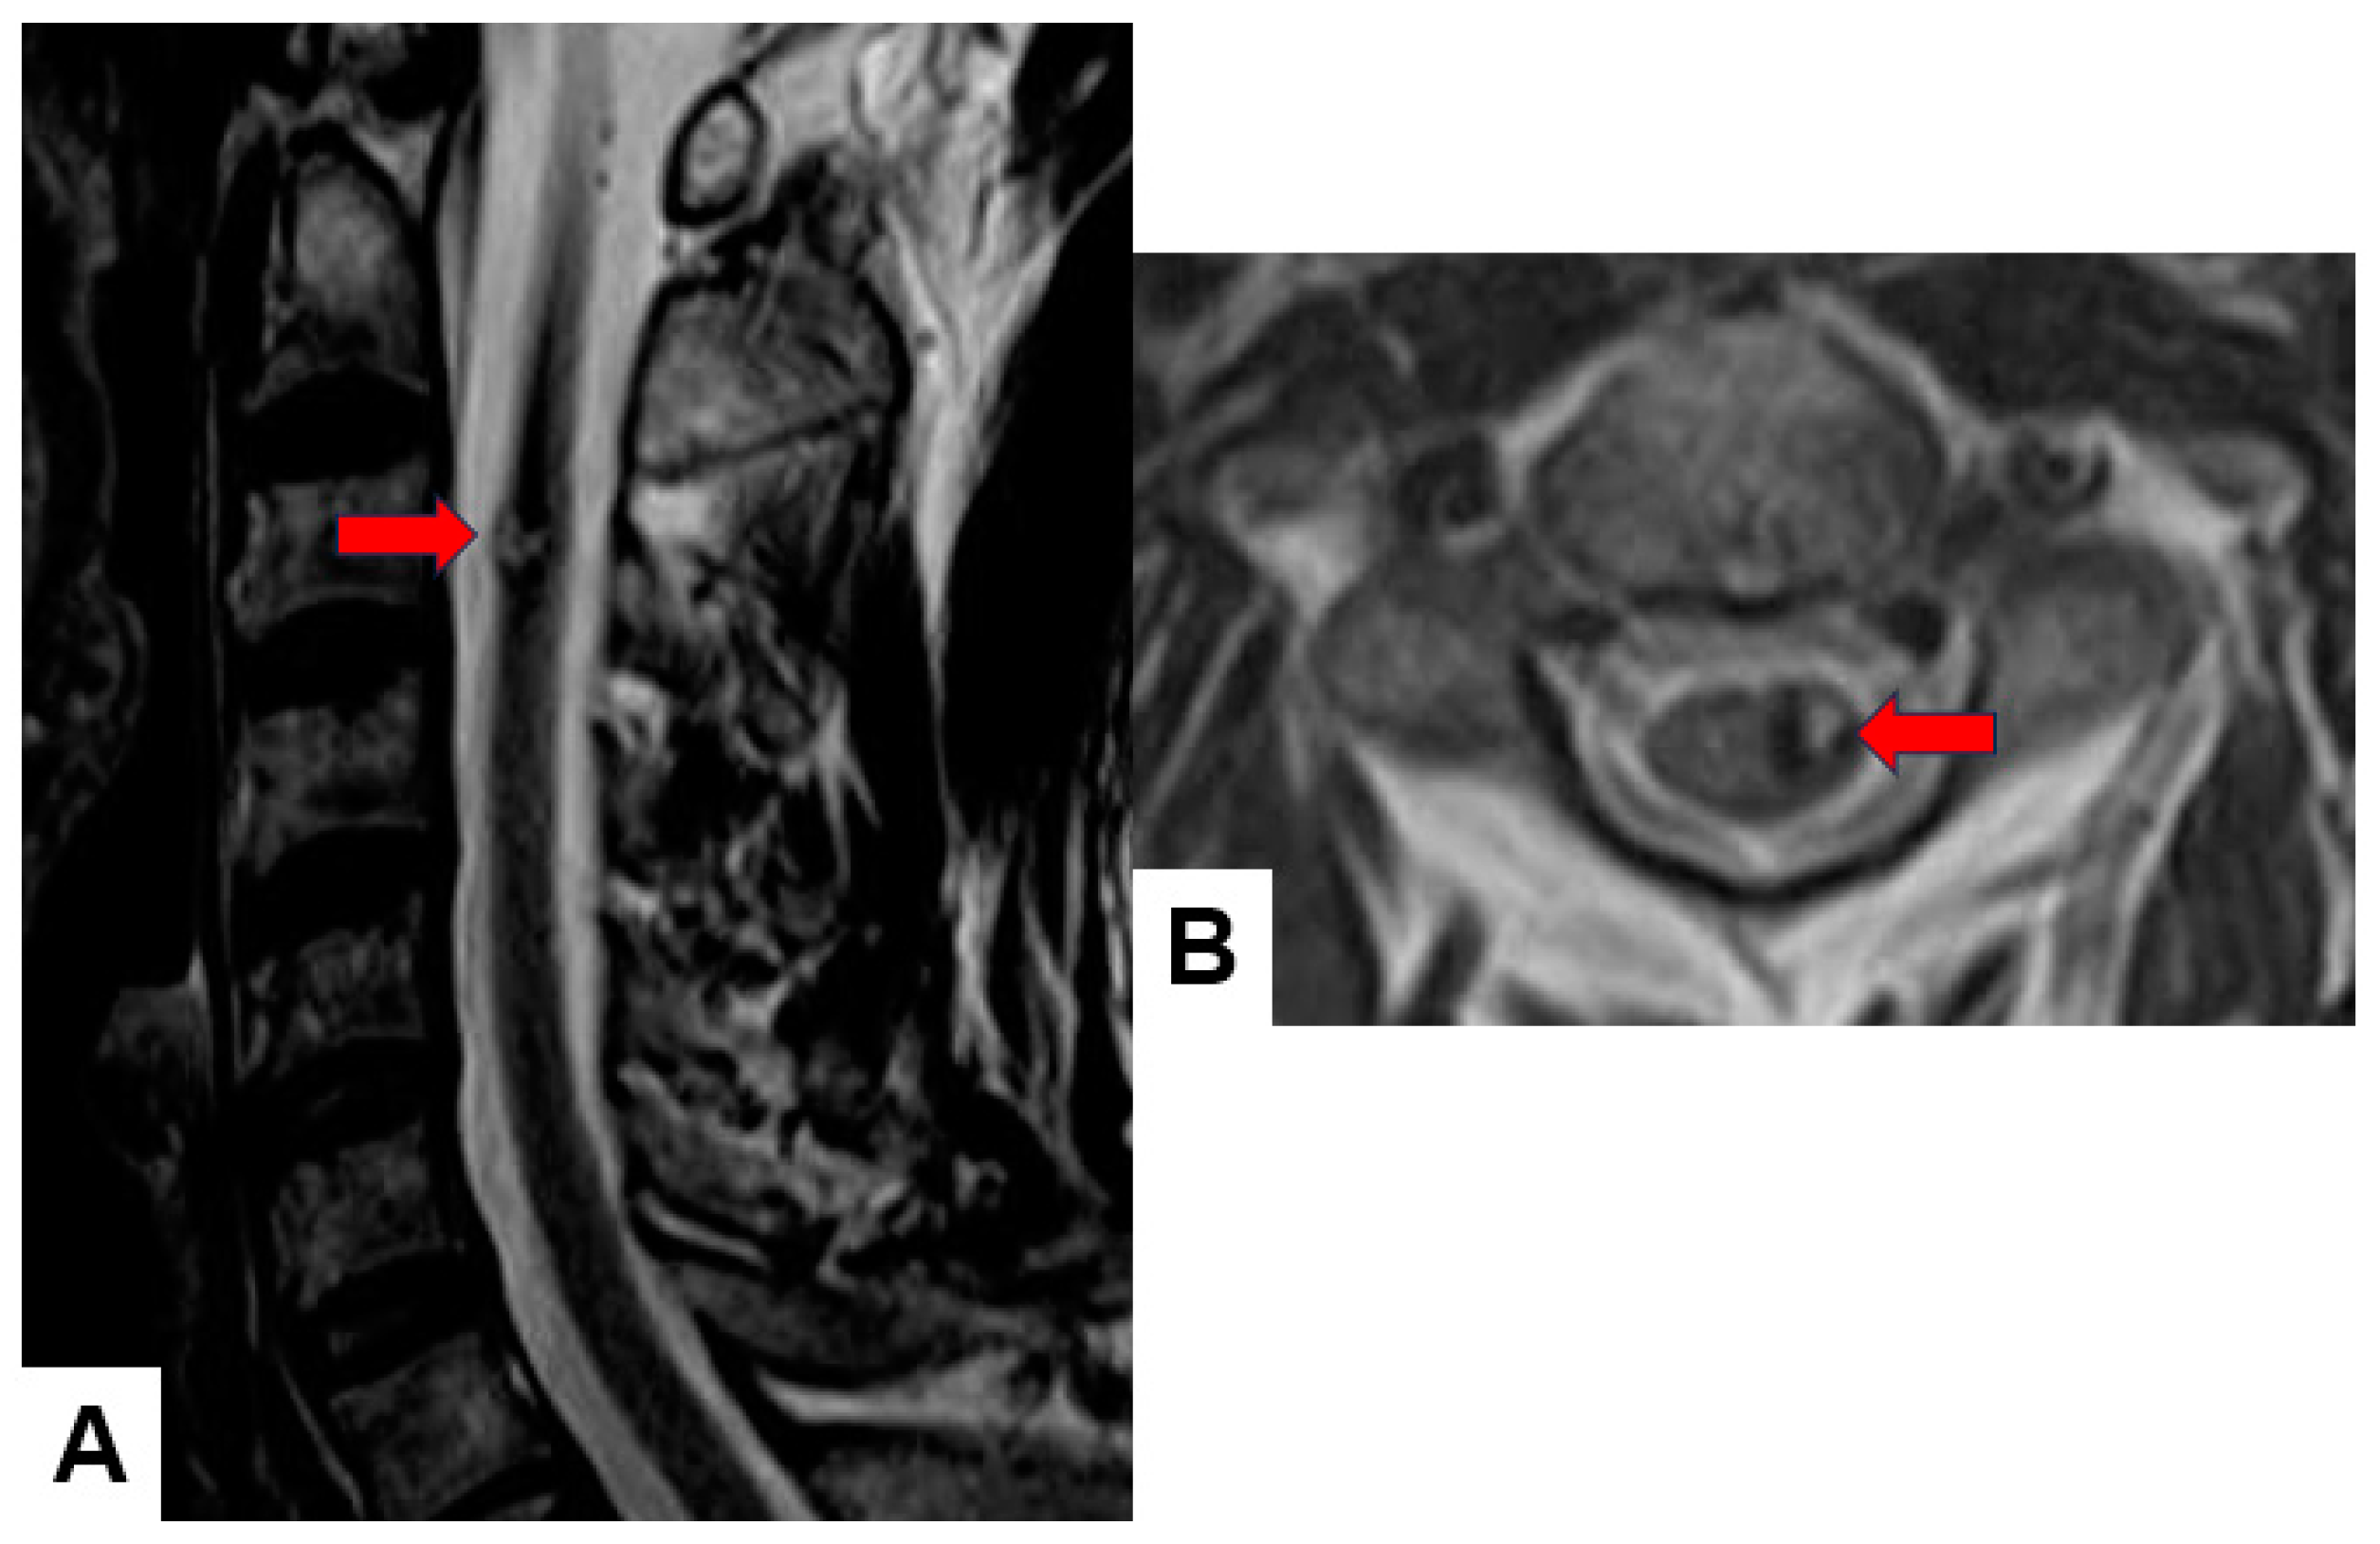

- Jung, J.S.; Choi, Y.S.; Ahn, S.S.; Yi, S.; Kim, S.H.; Lee, S.K. Differentiation between spinal cord diffuse midline glioma with histone H3 K27M mutation and wild type: Comparative magnetic resonance imaging. Neuroradiology 2019, 61, 313–322. [Google Scholar] [CrossRef] [PubMed]